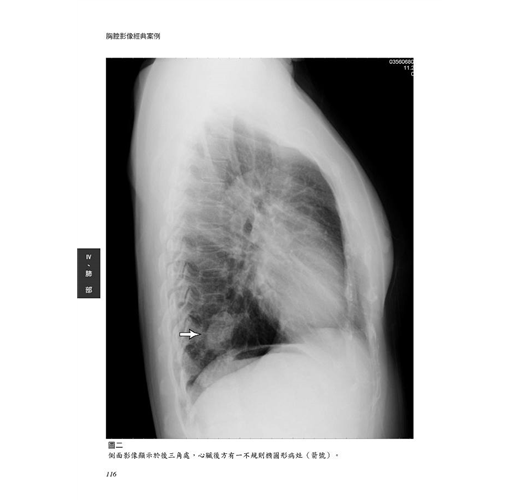

病例26 肺葉內游離肺(Intralobar pulmonary sequestration) 115

病例27 淋巴管平滑肌增生症(Lymphangiomyomatosis, LAM) 120